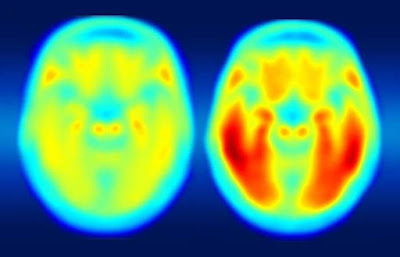

A pesquisa tem como objetivo criar um tratamento para remover placas beta-amiloides (Abeta) acumuladas e emaranhados neurofibrilares compostos pela proteína tau hiperfosforilada - juntas, essas anomalias levam à neurodegeneração e ao declínio cognitivo característicos da doença de Alzheimer. Essa é a principal causa de demência relacionada à idade. Os principais desafios são a falta de tratamentos eficazes, biomarcadores confiáveis ou estratégias preventivas.

As possíveis novas terapias foram testadas em camundongos bigênicos que apresentavam tanto o acúmulo da beta-amiloide quanto os emaranhados neurofibrilares. A nova abordagem combinada com vacinação poderia ser usada para induzir “fortes respostas imunes a ambas as patologias marcantes da doença de Alzheimer em uma ampla base populacional de indivíduos com polimorfismos genéticos de classe II de MHC”, diz o artigo. Essas pessoas estão em risco de desenvolvimento da enfermidade. Os cientistas pretendem começar os testes em humanos em até dois anos.